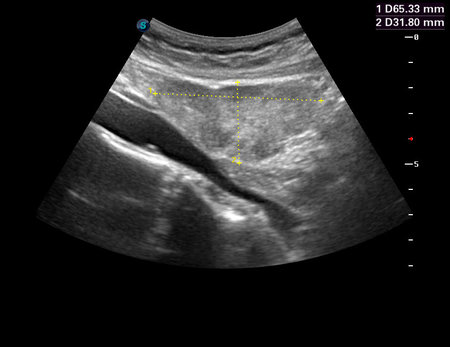

Молодая женщина, часто боли внизу живота справа, лежала несколько раз в гинекологическом отделении.

Мезогастриум справа.

Огромный полип толстой кишки.

Выполнена колоноскопия, обнаружено внутрикишечное образование больших размеров, взята гистология.

Затем полип удалили вместе с частью кишки.

Гистология - тубулярно-ворсинчатая аденома (tubulovillous adenomas).